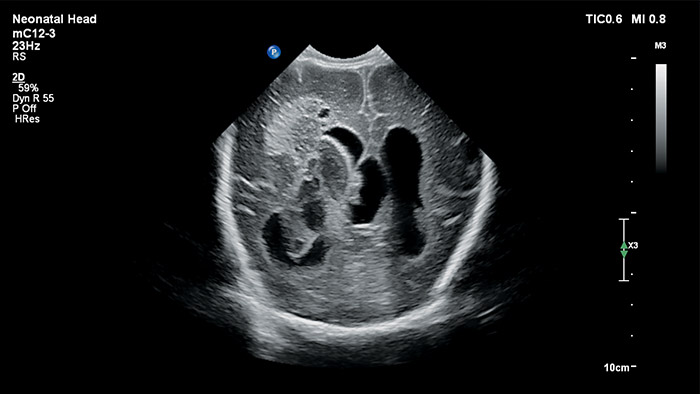

小児患者のイメージング用に最適化された世界初の優れたPureWaveトランスジューサファミリーを提供します。従来の小児用トランスジューサと比較して、ペネトレーションがさらに30%向上することが示されています。*

MicroFlow Imaging(MFI)は、高いフレームレートと2D画質を維持しながら、アーチファクトを低減する技術です。この技術によって、MFI HDの感度と分解能は標準的なMFI**の2倍を上回り、多くの小児臨床アプリケーションにおける血流の詳細な観察に最適です。